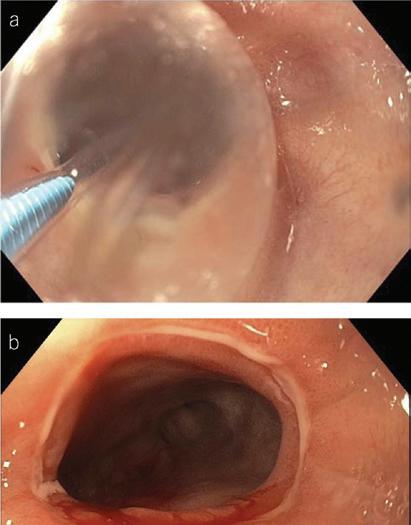

In a 1991 report in The American Journal of Gastroenterology, Drs. Alemayehu and Järnerot challenge prior orthodoxy that colonoscopy is contraindicated in patients with severe ulcerative colitis.